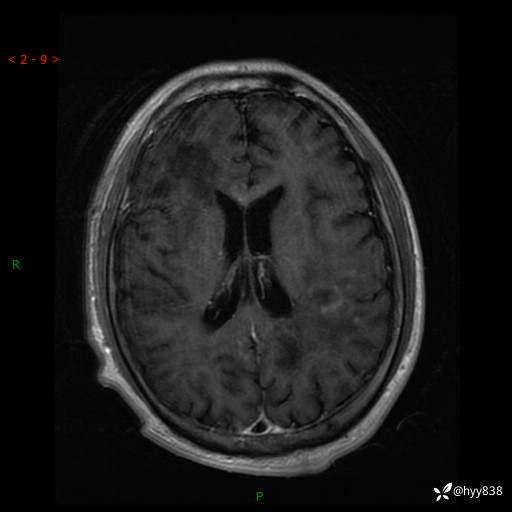

辅助检查:MRI

MRI T2WI